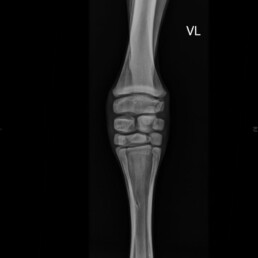

In der röntgenologischen Untersuchung der Tarsi und Carpi wurde eine hypoplastische Ossification Grad 2-3 festgestellt (schwach entwickelte Verknöcherung).

Abb. 2 – 0° rechte Vordergliedmaße: inkomplette Ossifikation der Carpalknochen Grad 2-3

Abb. 3 – 0° linke Vordergliedmaße: inkomplette Ossifikation der Carpalknochen Grad 2-3

Nach vier Wochen wurden Kontrollaufnahmen der Gliedmaßen angefertigt. Hier ist im Vergleich zu den vorherigen Aufnahmen ein deutliches Voranschreiten der Ossifikation zu erkennen, jedoch ist die Ossifikation weiterhin unvollständig (Abb. 3 und Abb. 4). An der rechten Vordergliedmaße besteht zudem ein Carpus valgus mit einer Achsenabweichung von 10°.

Abb. 3 Tarsus links 90°: Hypoplastische Ossifikation Grad IV

Abb. 4 Carpus links 0°: Hypoplastische Ossifikation Grad IV